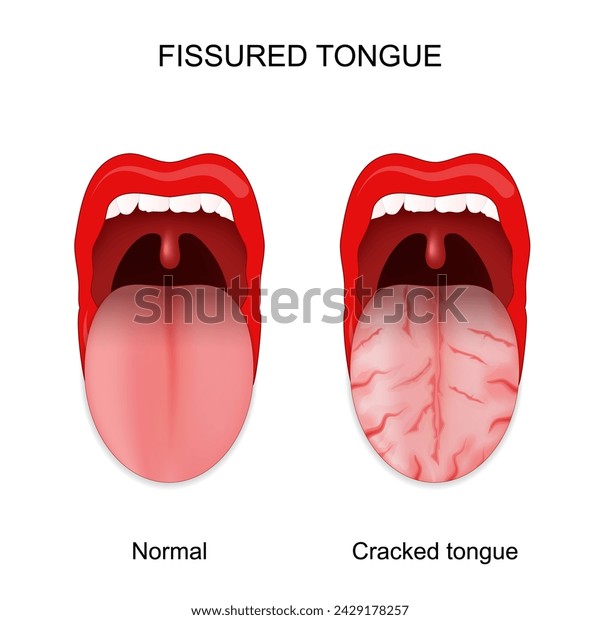

ベロ亀裂 (458 無料画像)

舌がひび割れるのはなぜ?原因や治療法を解説 - 武蔵中原の歯医者なら、中林デンタルケアークリニック武蔵中原駅徒歩5分の歯科医院。

舌がひび割れしてる?考えられる原因や対策について解説します! - 口腔外科DOC。

舌に亀裂がある カンジダ症 カンディダ 先天性病理学 — ストック写真 © natali_ploskaya430965280。

ひび割れた舌のイラスト素材105451846- PIXTA。

舌がひび割れしてる?考えられる原因や対策について解説します! - 口腔外科DOC。

舌に溝がある これって大丈夫?溝状舌の正体と対応法。

舌がひび割れるのはなぜ?原因や治療法を解説 - 武蔵中原の歯医者なら、中林デンタルケアークリニック武蔵中原駅徒歩5分の歯科医院。

舌に溝がある これって大丈夫?溝状舌の正体と対応法。

舌にひび割れがある」ときの体質・体調 - 漢方ライフ- 漢方を始めると、暮らしが変わる。

細菌感染症の舌、舌はつぐみ、亀裂舌写真素材368053802Shutterstock。

溝状舌 こうじょうぜつ とは 溝状舌の痛みの原因と対処法。

細菌感染の病気舌、舌はツグミです。舌の傷します。亀裂舌の写真素材・画像素材 Image 66956292。

舌がひび割れしてる?考えられる原因や対策について解説します! - 口腔外科DOC。

舌のひび割れはなぜ起きる?原因と対処法について徹底解説! – ココシカ。

病気サイン?舌がひび割れる4つの原因。溝状舌・ドライマウスはどう治す?病院は何科?Medicalook メディカルック。

舌のひび割れはなぜ起きる?原因と対処法について徹底解説! – ココシカ。

舌がひび割れるのはなぜ?原因や治療法を解説 - 武蔵中原の歯医者なら、中林デンタルケアークリニック武蔵中原駅徒歩5分の歯科医院。

舌がひび割れるのはなぜ?原因や治療法を解説 - 武蔵中原の歯医者なら、中林デンタルケアークリニック武蔵中原駅徒歩5分の歯科医院。